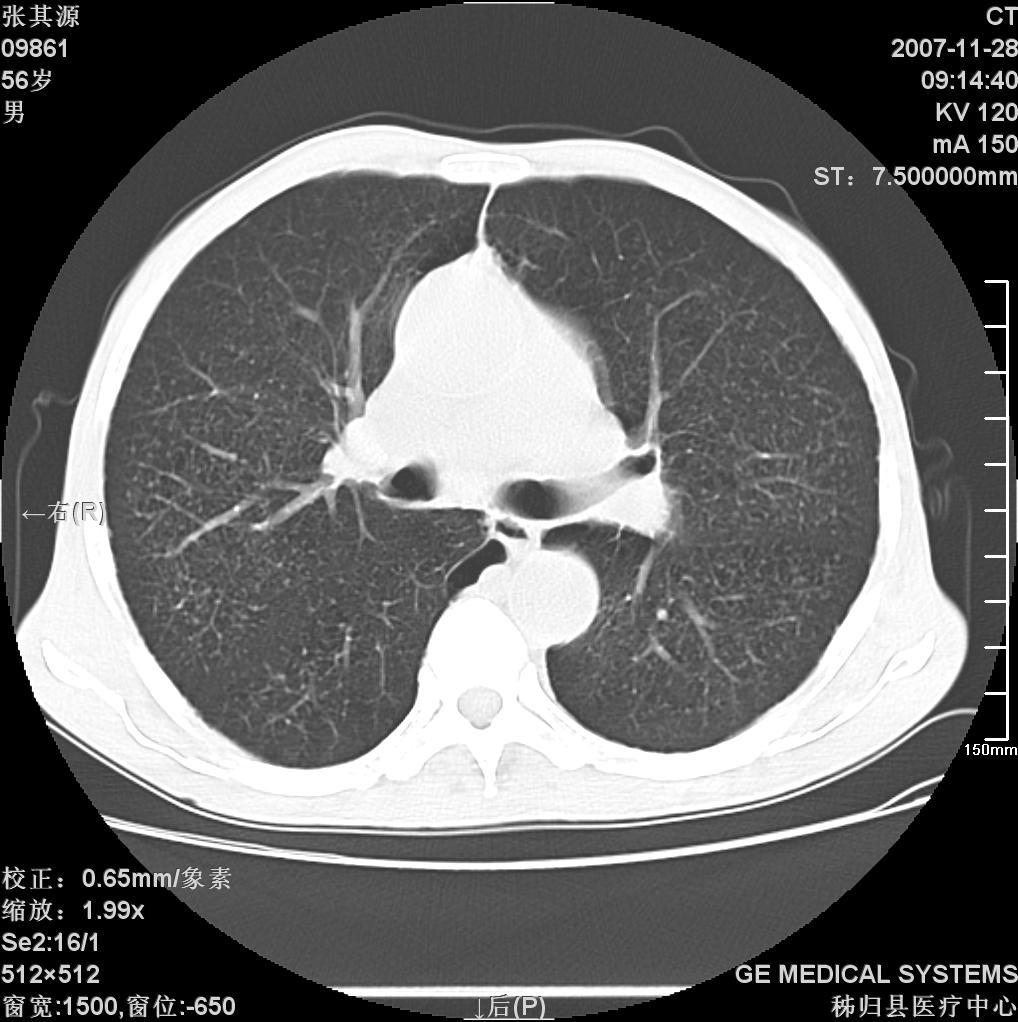

患者因阻塞性黄疸入院,发病前10天持续中等程度发烧.术前检查发现两肺弥漫性病变,请各位大虾会诊,除了考虑急性血源性肺结核外,还有其他什么疾病可能.

补充一下,该患者没有与尘肺相关职业史。请大家帮忙会诊一下,外科医生打算为其做胆总管肿瘤做手术的,现在在等我们的结果。谢谢各位了。

双肺多发粟粒样病灶,右肺胸膜下结节样病灶,气管前腔静脉后及隆突下均见肿大淋巴结,结合胆道肿瘤病史首先考虑转移。另外心影密度略低,时间格显示,是否有贫血?查明白再手术吧!